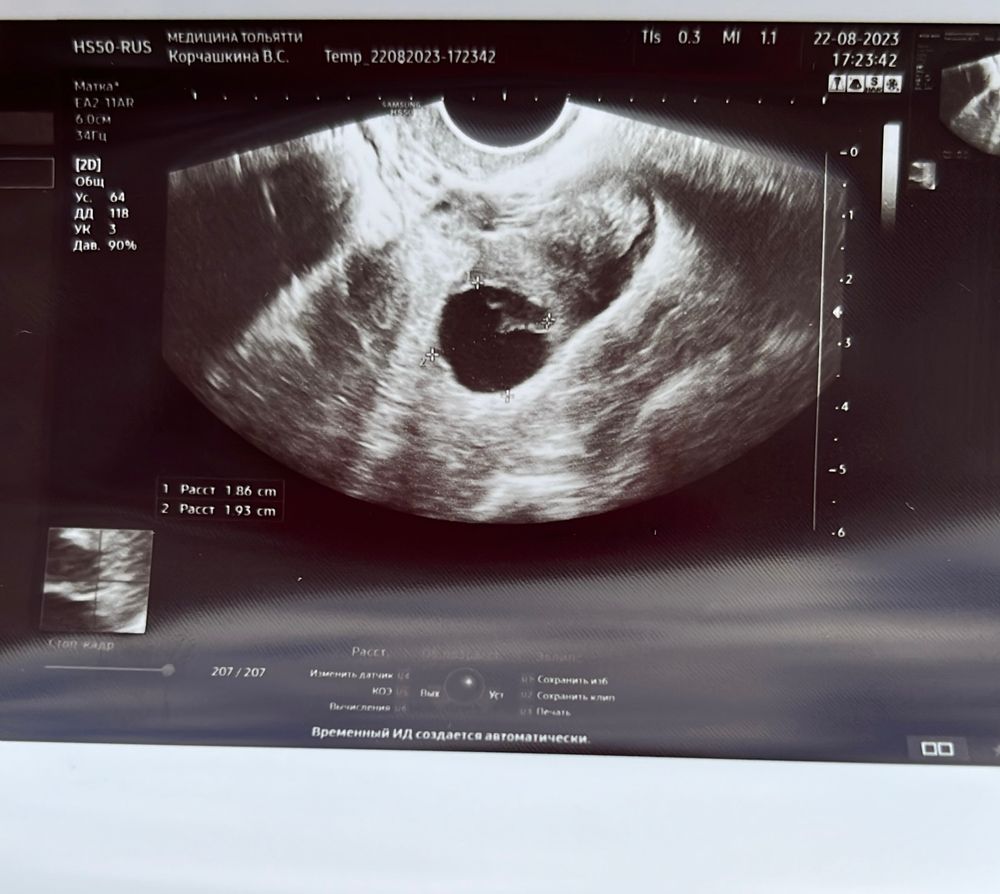

На 17 дц был красивый, ровный фолликул 19мм. В этот же день был укол ХГЧ 5000. Сейчас 23 дц, по узи врач не поняла жт или нет, очень сомневалась, но все же написала, что жт, но измененное. Сказала не может на 100% утверждать, что состоялась качественная овуляция и яйцеклетка вышла. Про жидкость тоже на словах сказала, что не увидела ее, в заключение пишет, что есть незначительно. Кровоток есть и не совсем ровное оно. Что думаете?

Возможно, произошла лютеинизация ЖТ